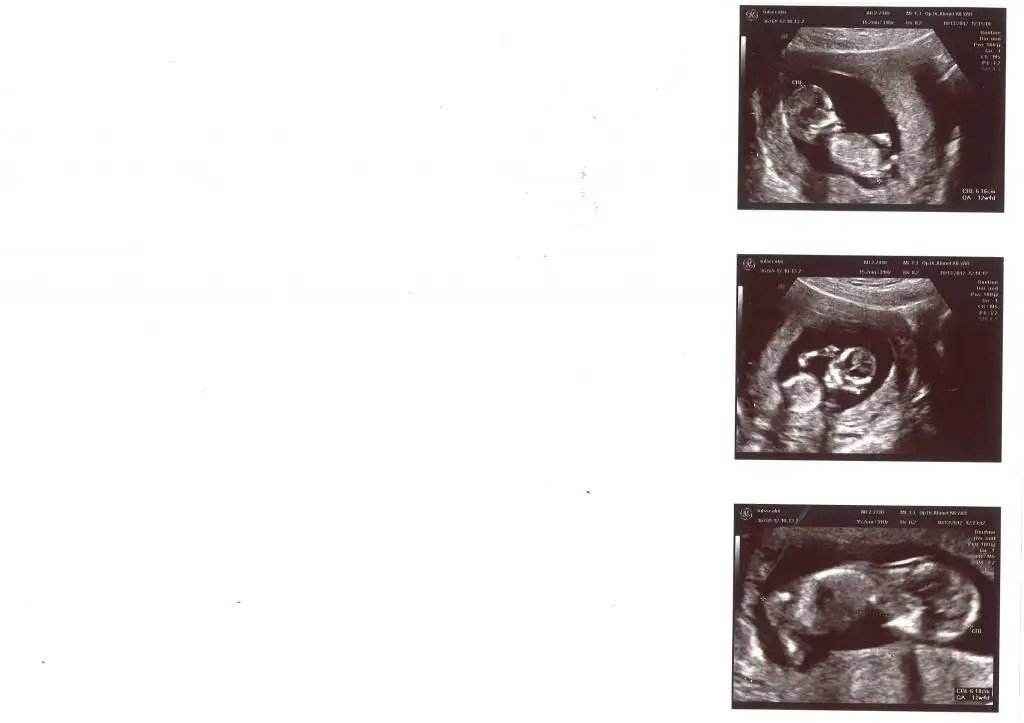

merhaba orkidem bunlar 20+1 deki fotolarım inşallah net şekilde görüyorsundur aslında bırakmıcaktım ama doktorumun tam net konuşmaması beni çok tereddüte sokuyor......son kontrolümde bebeğim tersti tam net olarak önden gözükmedi,doktora cinsiyetini sordum allttan ama zorla baktı bana söylediklerini aynen yazıyorum (kıza benziyor kız gibi kız herhalde)gözlerini kısarak ekrana bakıyordu bende emin olamıyorum tam net birşey demesini istiyorum.........sence kıza benziyormu şu anda kız fikrine çok alıştım herkesede söyledim ama eminde olamıyorum........fotolarla ilgili bir fikir verebilirsin inşalllah

canım 20.haftadan önce hiç yorum yapmadımı doktorun.yani ilk defamı yorum yaptı cinsiyeti hakkında.bacak arası boş gibi.yani şuanki bebeğimde benim öyle ultrason fotoğraflarında.ama senin fotoğraflar çok parlamış.bakalım işin uzmanı orkdm gelsin ne diyecek....

Resim net degil cnm bacak tarafi cok parlak cikmis

nubbahar banada bacak arasi bos gibi geldi ikinci fotoda

merhaba arkadaşlar bugün doktordaydım bebeği banada gösteriyordu fl ölçerken alttan baktı her iki bacak arasından hiç birşey göremedim kız olduğuna kanaat getirdim ve doktora tekrar sorma gereği duymadım çünkü önceki kontrolde kıza benzediğini söylemişti...........1 hafta öncesine kadar karmaşık duygular içindeydim ama şu an ne hissettiğimi tam olarak biliyorum hayalini bile kuramadığım birşeyi inşallah ikinci defa tadacağım ben daha neyin hesabını yapıyorum.........artık sadece gülistanımla kızkardeşinin tekmelerinin her anının tadını çıkarıyoruz.........inşallah doğumdan sonrada burdan mutluluk fotolarımızı paylaşırız